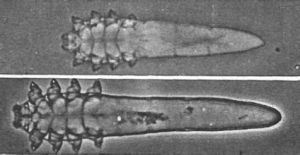

面部蟎蟲 蟎蟲(蠕形蟎)寄生人體的有毛囊形蟎和脂形蟎兩種,蟎蟲細長呈蠕蟲狀,體長0.1~0.2mm軀體的前部有齶體和點,整肢呈短針狀。較多的研究資料表明,我國人體蠕形蟎的感染率較高,據報導最高達到98%以上。因為人體對蟎蟲的感染無免疫性,不同年齡,不同民族,不同性別均可感染。